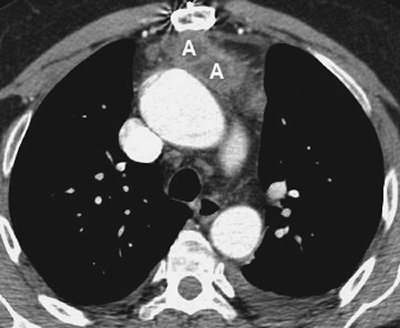

FIGURE 6-21. Hodgkin lymphoma. A: CT scan of a 59-year-old man with shortness of breath shows a homogeneous mass of soft tissue attenuation (M) compressing the left atrium (LA), nearly encasing the aorta (A), and abutting the esophagus (dashed arrow) and azygous vein (solid arrow). There is also a right pleural effusion (E). B: CT scan at a more inferior level shows retrocrural lymphadenopathy (A).